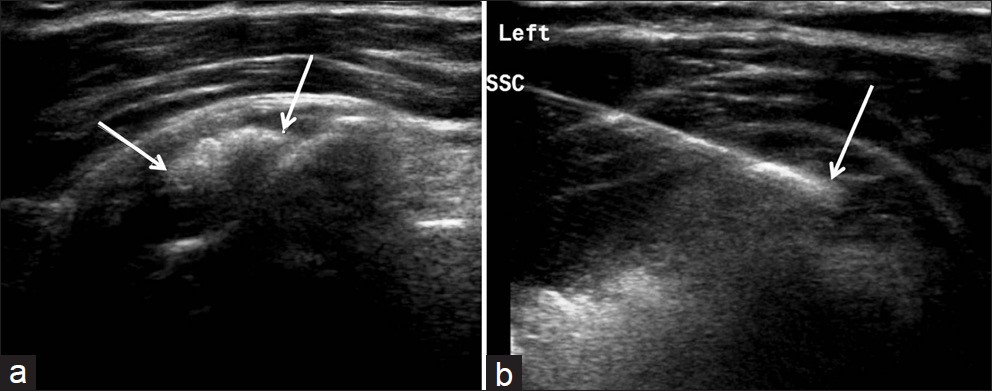

Poleg kliničnega pregleda je potrebna RTG diagnostika in UZ preiskava ramena, v določenih primerih tudi preiskava z magnetno resonanco. Običajno se vnetje zdravi s počitkom, analgetično terapijo, fizikalno terapijo. V določenih primerih svetujemo tudi terapijo z udarnimi valovi (ESWT).

V kolikor so kalcinati večji od 8mm in so enakomerne strukture lahko pod ultrazvočno kontrolo opravimo tudi punkcijo kalcinata in kalcinat izperemo. Poseg se opravi v lokalni anesteziji in traja približno 30 minut. Bolečina lahko traja tudi nekaj dni po posegu. V teh primerih svetujemo jemanje analgetikov. Nekaj dni po posegu priporočamo postopno stopnjevanje aktivnosti, izvajanje vaj, plavanja, nordijske hoje in fizikalne terapije in po 2 -3 mesecih vrnitev željenim aktivnostim.